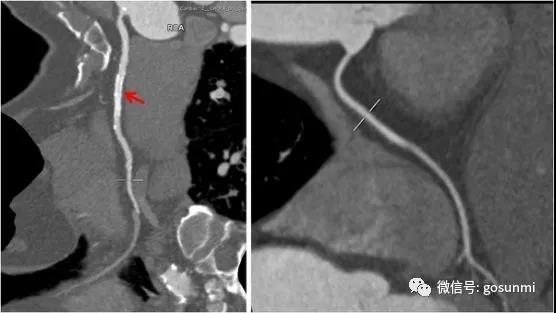

對(duì)于冠心病行冠脈支架植入術(shù)后的患者來(lái)說(shuō),也可以通過(guò)冠脈CTA檢查來(lái)觀察與評(píng)估支架的通暢情況等。如下圖所示,左圖顯示右冠的支架通暢,右側(cè)為正常右冠。